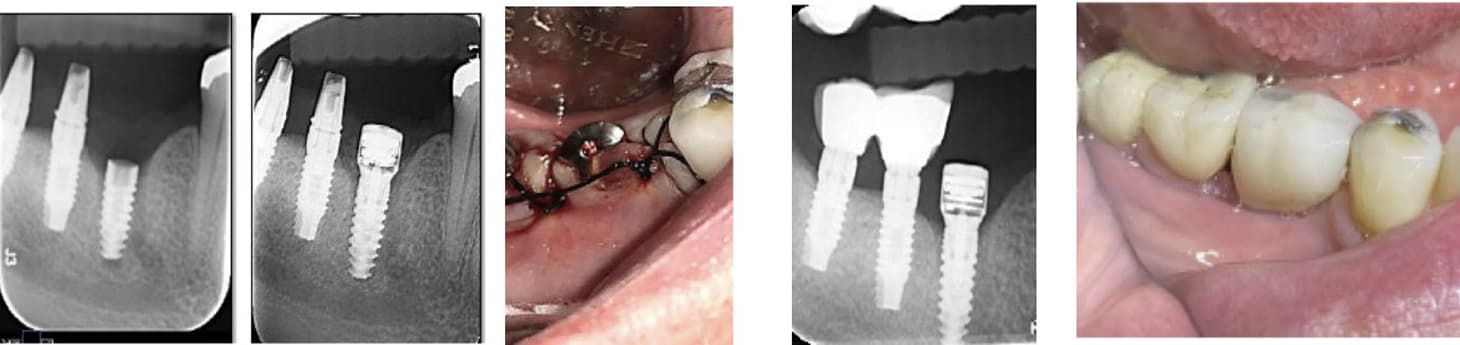

This case, performed by Prof. Alberto Monje, involved a patient diagnosed with inflammatory environment, presenting with advanced bone loss and bleeding on probing. The treatment followed a surgical regenerative protocol combining mechanical decontamination and biological stimulation using the MAGDENT Miniaturized Electromagnetic Device (MED). The procedure included implantoplasty, thorough surface debridement and decontamination, and guided bone regeneration (GBR) with a particulate bone graft and collagen membrane to restore the lost peri-implant bone structure. Immediately after the regenerative procedure, the MED healing abutment was connected to the implant and left in place for three weeks, delivering continuous pulsed electromagnetic field (PEMF) stimulation to promote cellular activation, angiogenesis, and bone remodeling at the defect site.

After soft tissue stabilization, the prosthesis was reinstalled, and long-term follow-up at 11 months demonstrated excellent clinical and radiographic outcomes. The treated site exhibited complete mucosal healing, absence of inflammation or pocketing, and stable bone regeneration with clear re-establishment of crestal bone levels around the implant. Radiographs confirmed maintenance of the regenerated bone volume and implant stability, while clinical evaluation showed healthy peri-implant tissues with ideal color, tone, and contour.

• This case highlights the effectiveness of the surgical inflammatory environment management protocol integrating PEMF technology, showing how the MED device can enhance bone regeneration and accelerate healing when combined with conventional regenerative techniques such as implantoplasty and GBR. The synergy between surgical decontamination and electromagnetic stimulation supports a predictable, biologically driven regeneration in peri-implant defects, offering a viable alternative to more invasive resection procedures.

Inflammatory environment Surgical Regeneration (Prof. Alberto Monje, DDS, MS, PhD) This clinical case, documented by Prof. Alberto Monje and published in Periodontology 2000 (“Emerging locally delivered antimicrobial and immunomodulatory approaches for the prevention/treatment of peri-implant diseases,” Monje et al., DOI: 10.1111/prd.12638), presents a surgically managed inflammatory environment defect with the integration of Magdent’s Miniaturized Electromagnetic Device (MED) as an adjunctive regenerative tool. The patient was diagnosed with inflammatory environment accompanied by inflammation and progressive bone loss (A–B). The disease had persisted despite prior nonsurgical therapy (C). During the surgical phase, granulation tissue was meticulously removed by curettage (D), and implantoplasty was performed on the exposed implant surface to smooth irregularities and reduce bacterial adhesion (E). Subsequent electrolytic decontamination of the intrabony area was performed using the GalvoSurge system (F), ensuring optimal surface disinfection prior to regeneration. Following decontamination, a guided bone regeneration (GBR) procedure was performed using a particulate bone graft, after which the Magdent PEMF healing abutment was immediately connected to the implant (G). The MED device delivered pulsed electromagnetic field (PEMF) stimulation over a period of three weeks, enhancing cellular activity, vascularization, and bone remodeling during the early healing phase.

At 9 months, clinical evaluation revealed complete soft tissue healing, resolution of inflammation, and reestablishment of mucosal seal (H). At 1-year follow-up, radiographs confirmed substantial bone regeneration and defect fill with stable crestal bone levels and restored implant function (I).

• This case underscores the clinical efficacy of combining regenerative surgery, decontamination, and electromagnetic stimulation. The synergy between implantoplasty, electrolytic cleaning, and Magdent PEMF therapy demonstrates a predictable, minimally invasive, and biologically enhanced approach to inflammatory environment management, providing both functional and histological regeneration outcomes in previously compromised implant sites.